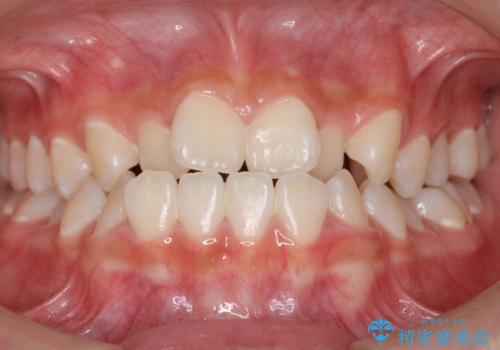

前歯のがたつき インビザラインで抜歯矯正

- 前歯のがたつきを主訴に来院。

右下の犬歯が歯ぐきが痩せて、歯肉退縮しておりそれを抜歯しました。

上の前歯はIPRを行なっています。

右下の犬歯の1本抜歯で最小限の抜歯で並べることができました。

奥歯も上下交互になるようにかみ合わせることができました。